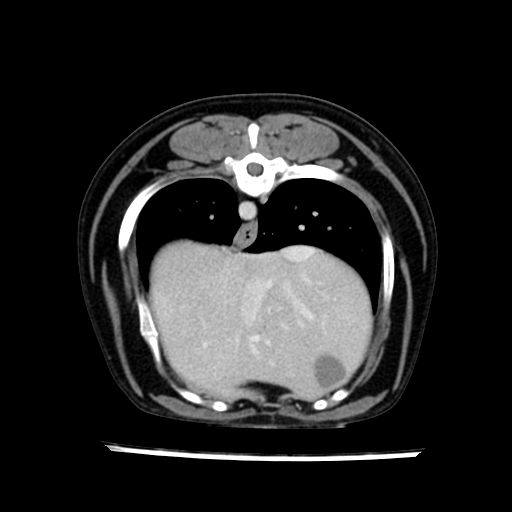

prescritto esame TAC

sequenza immagini limitata al fegato reni e surreni

le immagini ecografiche rispetto alla tac datano circa 7 mesi prima ,le surrenali sono normali nonostante il test acth sia risultato positivo .all’esame TAC dopo diversi mesi risultano aumentate armonicamente nel volume e si individua un forte sospetto di adenoma ipofisario .

sospetto adenoma ipofisario vs. meno probabilmente meningioma della base; intertiziopatia polmonare; lesione espansiva epatica, verosimilmente del lobo laterale sinistro, di sospetta natura neoplastica; lesioni spleniche di natura da definire; iperplasia/ipertrofia delle ghiandole surrenali, bilateralmente; vertebra di transizione del rachide toracico; tenosinovite cronica del muscolo bicipite brachiale di destra.